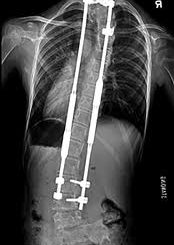

Manyetik çubuklar SMA hastası çocuklarda güvenli ve etkili görünüyor

Yapılan bir araştırmaya göre, omurgaya yerleştirilen ve çocuk büyüdükçe dışarıdan mıknatıs yardımıyla ayarlanabilen özel destek çubukları, 1. tip SMA hastası olan çocuklarda omurga eğriliğini kontrol […]